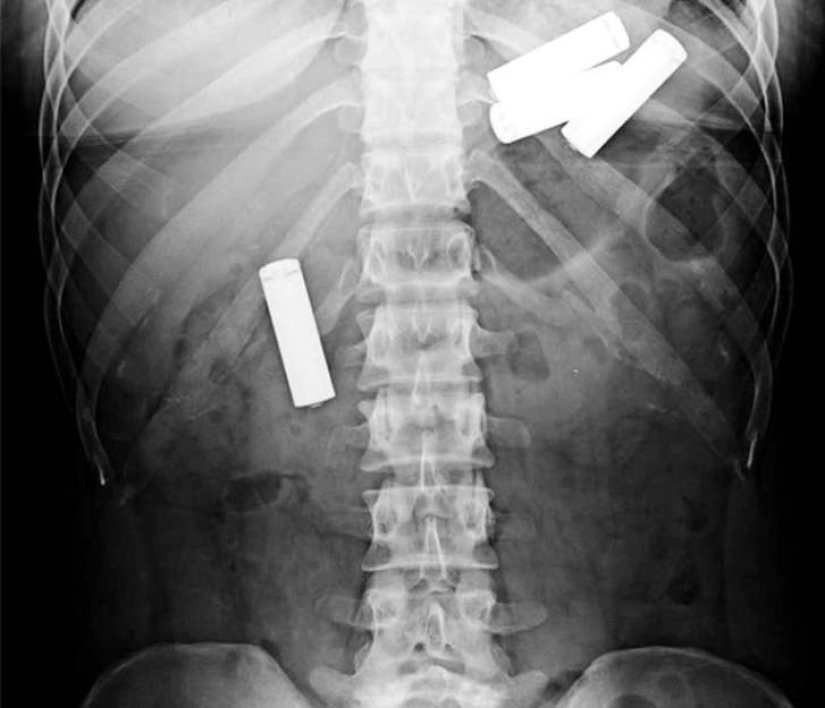

13. Y aquí están las pilas!